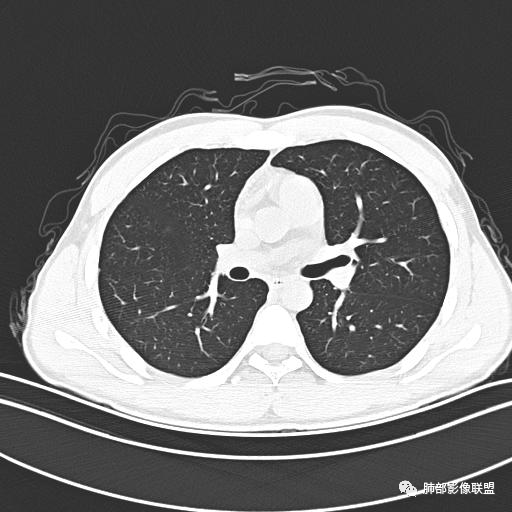

男,19岁

主  诉:发热、全身皮疹2天。

现病史:患者源于2天前受凉后出现发热,最高体温为38.5℃,且颜面部出现少量皮疹,无鼻塞、流涕、咳嗽、咳痰,未在意而未作特殊处理,次日全身皮疹逐渐增多至全身,伴轻度瘙痒,在当地卫生所给予抗病毒、抗感染治疗(具体用药不详)体温有所下降,但皮疹无明显消退,无腹痛、头痛,食欲无明显减退,为进一步诊治,遂于今日急来我院求治,患者目前精神尚可,体力正常,食欲正常,睡眠正常,体重无明显变化,大便正常,排尿正常。

小强:青年,发热,皮疹;双肺散在结节,周围磨玻璃,点晕征,疱疹病毒感染,鉴别荚膜组织胞浆菌,结核。 大雄:青年,急性起病,发热伴全身皮疹2天,抗病毒治疗体温有下降。双肺随机分布大小不等类圆结节,“点晕征”。考虑水痘-疱疹病毒(VZV)血播询问接触史,查体皮疹分布以及形态基本可诊断。 王开金江津中心医院呼吸科:青年男性,起病急,病程短,以发热,皮疹为首发症状,感染指标以单核细胞升高为主,胸部ct双肺多发结界,周围有晕,点晕表现,随机分布,同意於老师意见,水痘疱疹病毒血流感染累及肺。 王秀仙:双肺多发大小不等结节,周围有晕,边缘模糊,呈点晕征表现。青年,急性起病,发热伴全身皮疹2天,抗病毒治疗体温有下降。考虑疱疹病毒。鉴别荚膜组织胞浆菌。 傅昌瑜:19岁男性,发热、全身皮疹2天,单核细胞增高,双肺多发结节,结节边缘见边界不清磨玻璃影。点晕征+发热、全身皮疹+单核细胞增高——考虑水痘-带状疱疹病毒肺炎。 一切∮随缘:年轻男性,发热,皮疹两天,实验室,CRP,PCT增高,影像:双肺多发散在磨玻璃结节,边界欠清,大小不等,呈点晕征改变,以血管束周围分布为主,局部血管束略增粗,其它无明显改变,考虑:1:病毒性肺炎(水痘疱疹病毒?不知道皮肤有无改变)2:真菌(组织胞浆菌,血管侵袭性肺曲霉)3:GPA4:寄生虫(实验室没有看到嗜酸细胞增高) 赵山河:双肺散在结节,周围有晕,边缘模糊,呈点晕征表现。青年,急性起病,发热伴全身皮疹2天,抗病毒治疗体温有下降。考虑水痘—疱疹病毒感染。洪桥爱:青年男性,发热、皮疹2天,伴瘙痒,皮疹于面部首发,之后进展至全身,虽然没有对皮疹进行描述,但是从出疹时间及皮疹进展情况,伴瘙痒,应该就是个水痘患者;CT提示双肺随机分布结节影,部分结节伴有边界不清晕征,考虑水痘血播肺。 刘强:年轻男性,急性起病,皮疹,发热,抗感染治疗体温下降,说明有效。影像表现为散在点晕征,感染类疾病谱(疱疹病毒,真菌,结核),结合年龄,皮肤皮疹,考虑水痘-疱疹病毒性肺炎。 小兜:男性,19岁,发热皮疹两天,颜面部至全身,CRP,降钙素及单核增高。CT示双肺散在小结节,周围伴磨玻璃影,点晕征,考虑为水痘-带状疱疹病毒(varicella-zoster virus,VZV)肺炎 必有路:青年,皮疹+发热+“点晕征”→水痘-疱疹病毒(VZV) 许慧良:青年男性患者,发热、皮疹2天,体温最高38.5℃,第3天皮疹扩展至全身,伴瘙痒,胸部CT:双肺多发随机分布的小结节,结节周边见边界模糊的晕征,考虑水痘病毒感染流心明智:男,19,急性起病,发热伴全身皮疹2天。出疹顺序头→全身,抗病毒有效。胸部CT:两肺多发大小不等类圆形实性小结节影,随机分布,结节周围环绕GGO,边界模糊,呈点晕征。出疹特点是关键,未提示。考虑:血播病毒性肺炎,水痘-疱疹病毒?麻疹?鉴别荚膜组织胞浆菌、TB、血管炎、寄生虫等。 浪迹天涯:病灶多为5-10mm大小结节,结节周围可见磨玻璃样的晕环,常多发,可分布于肺内任何区域,考虑水痘—带状疱疹病肺炎如果短时间内有新的一个区域浸润,更加能说明,